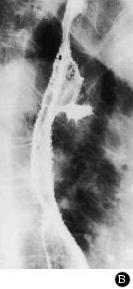

Image de TOGD et double de

contrast transit oesophagien avec aspect crenele de

paroie de oesophage + image des ulceres stagnant de

baryte |

Aspect

crenele de paroie de oesophage avec image des

ulceres etendue alonge l'oesophage |